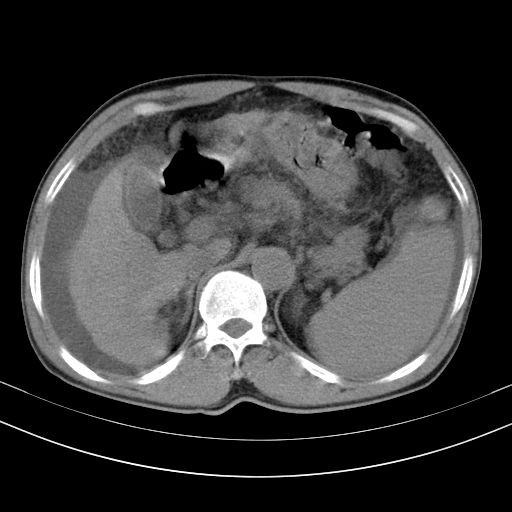

以下是引用随光逐影在2010-2-28 10:23:00的发言:[br]1)考虑肝癌;建议行ct增强扫描检查。2)肝硬化,脾大,腹水。3)慢性胆囊炎。

以下是引用dyqct在2010-2-28 16:44:00的发言:[br][quote]以下是引用随光逐影在2010-2-28 10:23:00的发言:[br]1)考虑肝癌;建议行ct增强扫描检查。2)肝硬化,脾大,腹水。3)慢性胆囊炎。